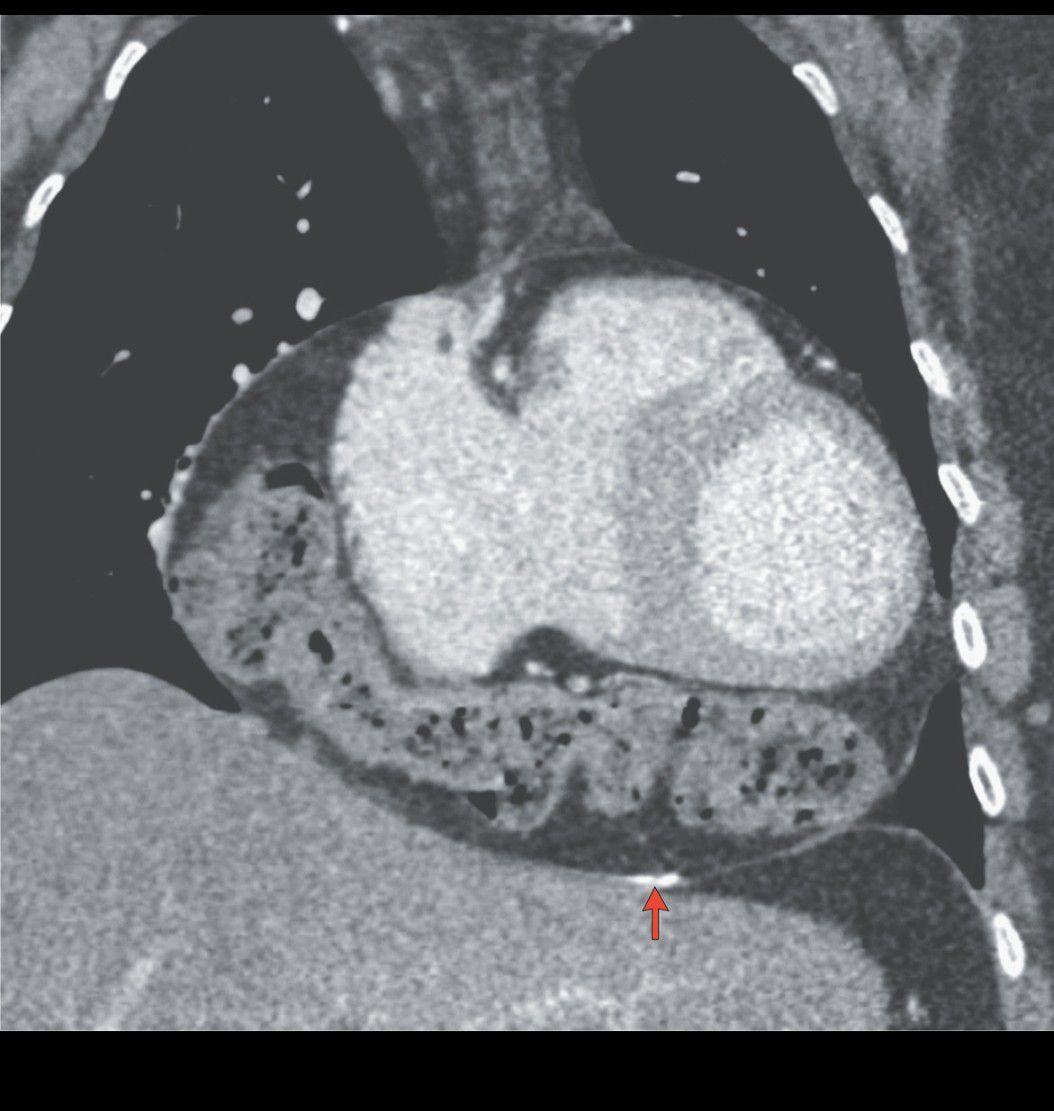

A 54-year-old woman presented to the emergency department with palpitations that she noted were relieved when she passed gas or had a bowel movement. Her medical history was notable for constrictive pericarditis that had occurred 15 years earlier and had been treated with pericardial drainage. Because of the atypical presentation, thoracic–abdominal–pelvic computed tomography with intravenous contrast material was performed, which revealed the presence of the transverse colon within the pericardial cavity. Pericardial calcification was also visible (arrow). Intrapericardial colon is considered to be a type of diaphragmatic hernia and in this case was thought to be related to the patient’s previous pericardial procedure. Laparoscopic surgery was performed to remove the colon from the pericardium, and silicone mesh material was used to repair the diaphragm. The patient was discharged 5 days after surgery. The palpitations resolved, and at follow-up 1 year later, she had had no recurrence.